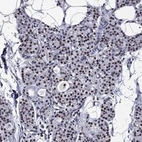

Immunohistochemical staining of human parathyroid gland shows strong nuclear positivity in glandular cells.